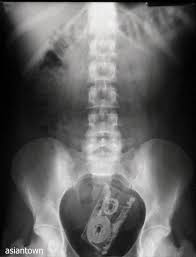

何かを誤食した犬のレントゲンでも稀にあるやつ。金属は本当に綺麗に写る。そういやついこの間、手術前にレントゲン撮ったら胃の中に何か金属が……で、正体は100円玉2枚だったんだが綺麗に重なっていたせいで、ボタン電池かもしれない!やべーぞ!!で内視鏡ある所に慌てて送られた犬もいたな。